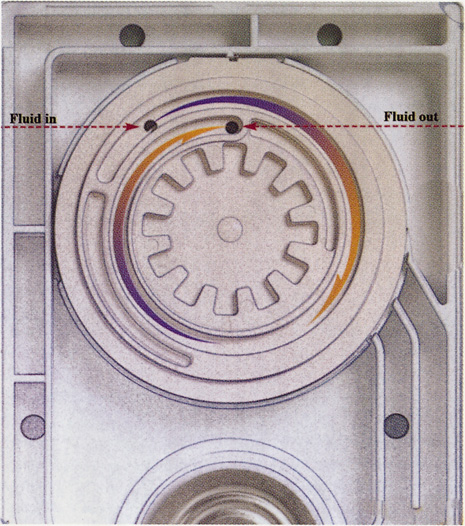

Although slit-lamp examination can give the ophthalmologist an excellent estimate of endothelial health, sometimes a formal assessment of the corneal endothelial cell density is helpful (Fig. 4). This information is most likely to be helpful in advising patients who may be at greater risk of postoperative corneal decompensation. Specifically, patients with cornea guttata, previous ocular surgery, history of blunt ocular injury,56 exfoliation syndrome,57 iridocorneal-endothelial syndromes,58 or a history of glaucoma59 are known to have reduced endothelial cell counts. Patients with a history of acute angle closure are at particular risk because each episode of elevated intraocular pressure can damage endothelial cells.60

There are qualitative and quantitative methods for endothelial cell evaluation. Cell density can be measured directly with an endothelial cell camera. The surgeon also should view the photograph and qualitatively estimate the regularity of the endothelial cell mosaic. Some instruments calculate a coefficient of variability and percent of hexagonal cells.

When an endothelial cell camera is not available, qualitative assessment of count and cell morphology can be accomplished at the slit-lamp using a technique called specular reflection.61 The ophthalmologist focuses a narrow parallelepiped on the corneal epithelium, directing the beam at the periapical cornea from a 45-degree angle. The slit beam is moved slowly from side to side until the bright corneal reflex strikes the examiner's view from the epithelial surface reflection (first Purkinje-Sanson image). On high magnification, the examiner should focus on the endothelial surface just next to the bright reflex. The image of the endothelial mosaic will come into view. The surgeon can make a qualitative assessment of the cell density and degree of regularity. With practice, these estimates can be surprisingly accurate.

The implications of a reduced endothelial cell count are primarily prognostic and can provide the surgeon with more information to help counsel the patient about the risk of corneal decompensation with cataract surgery. Gentle phacoemulsification without triple procedure is recommended when cornea is clear and compact, given that a significant number of patients may be able to avoid a corneal transplant despite uncountable cell densities. However, these patients should be advised that they may be at an increased risk of requiring a corneal transplant.